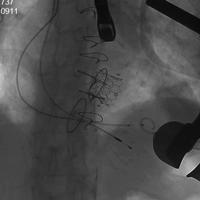

病例五(经股动脉主动脉瓣瓣中瓣)

患者男性,71岁,胸痛、气短半年,近一月加重,既往行主动脉瓣生物瓣置换术,置入HANCOCK II 21#瓣膜。术前心脏超声示主动脉瓣生物瓣衰败,主动脉瓣重度狭窄并中度关闭不全,峰值流速3.8m/s,平均跨瓣压差23mmHg。STS评分8.046%,属于外科换瓣手术高风险患者。术中经股动脉途径植入19#Renato球扩式瓣中瓣,释放成功后瓣膜功能良好,无瓣周漏及瓣中反流。峰值流速降至2.5m/s,平均跨瓣压差降至12mmHg。

瓣膜释放 术后主动脉根部造影无反流